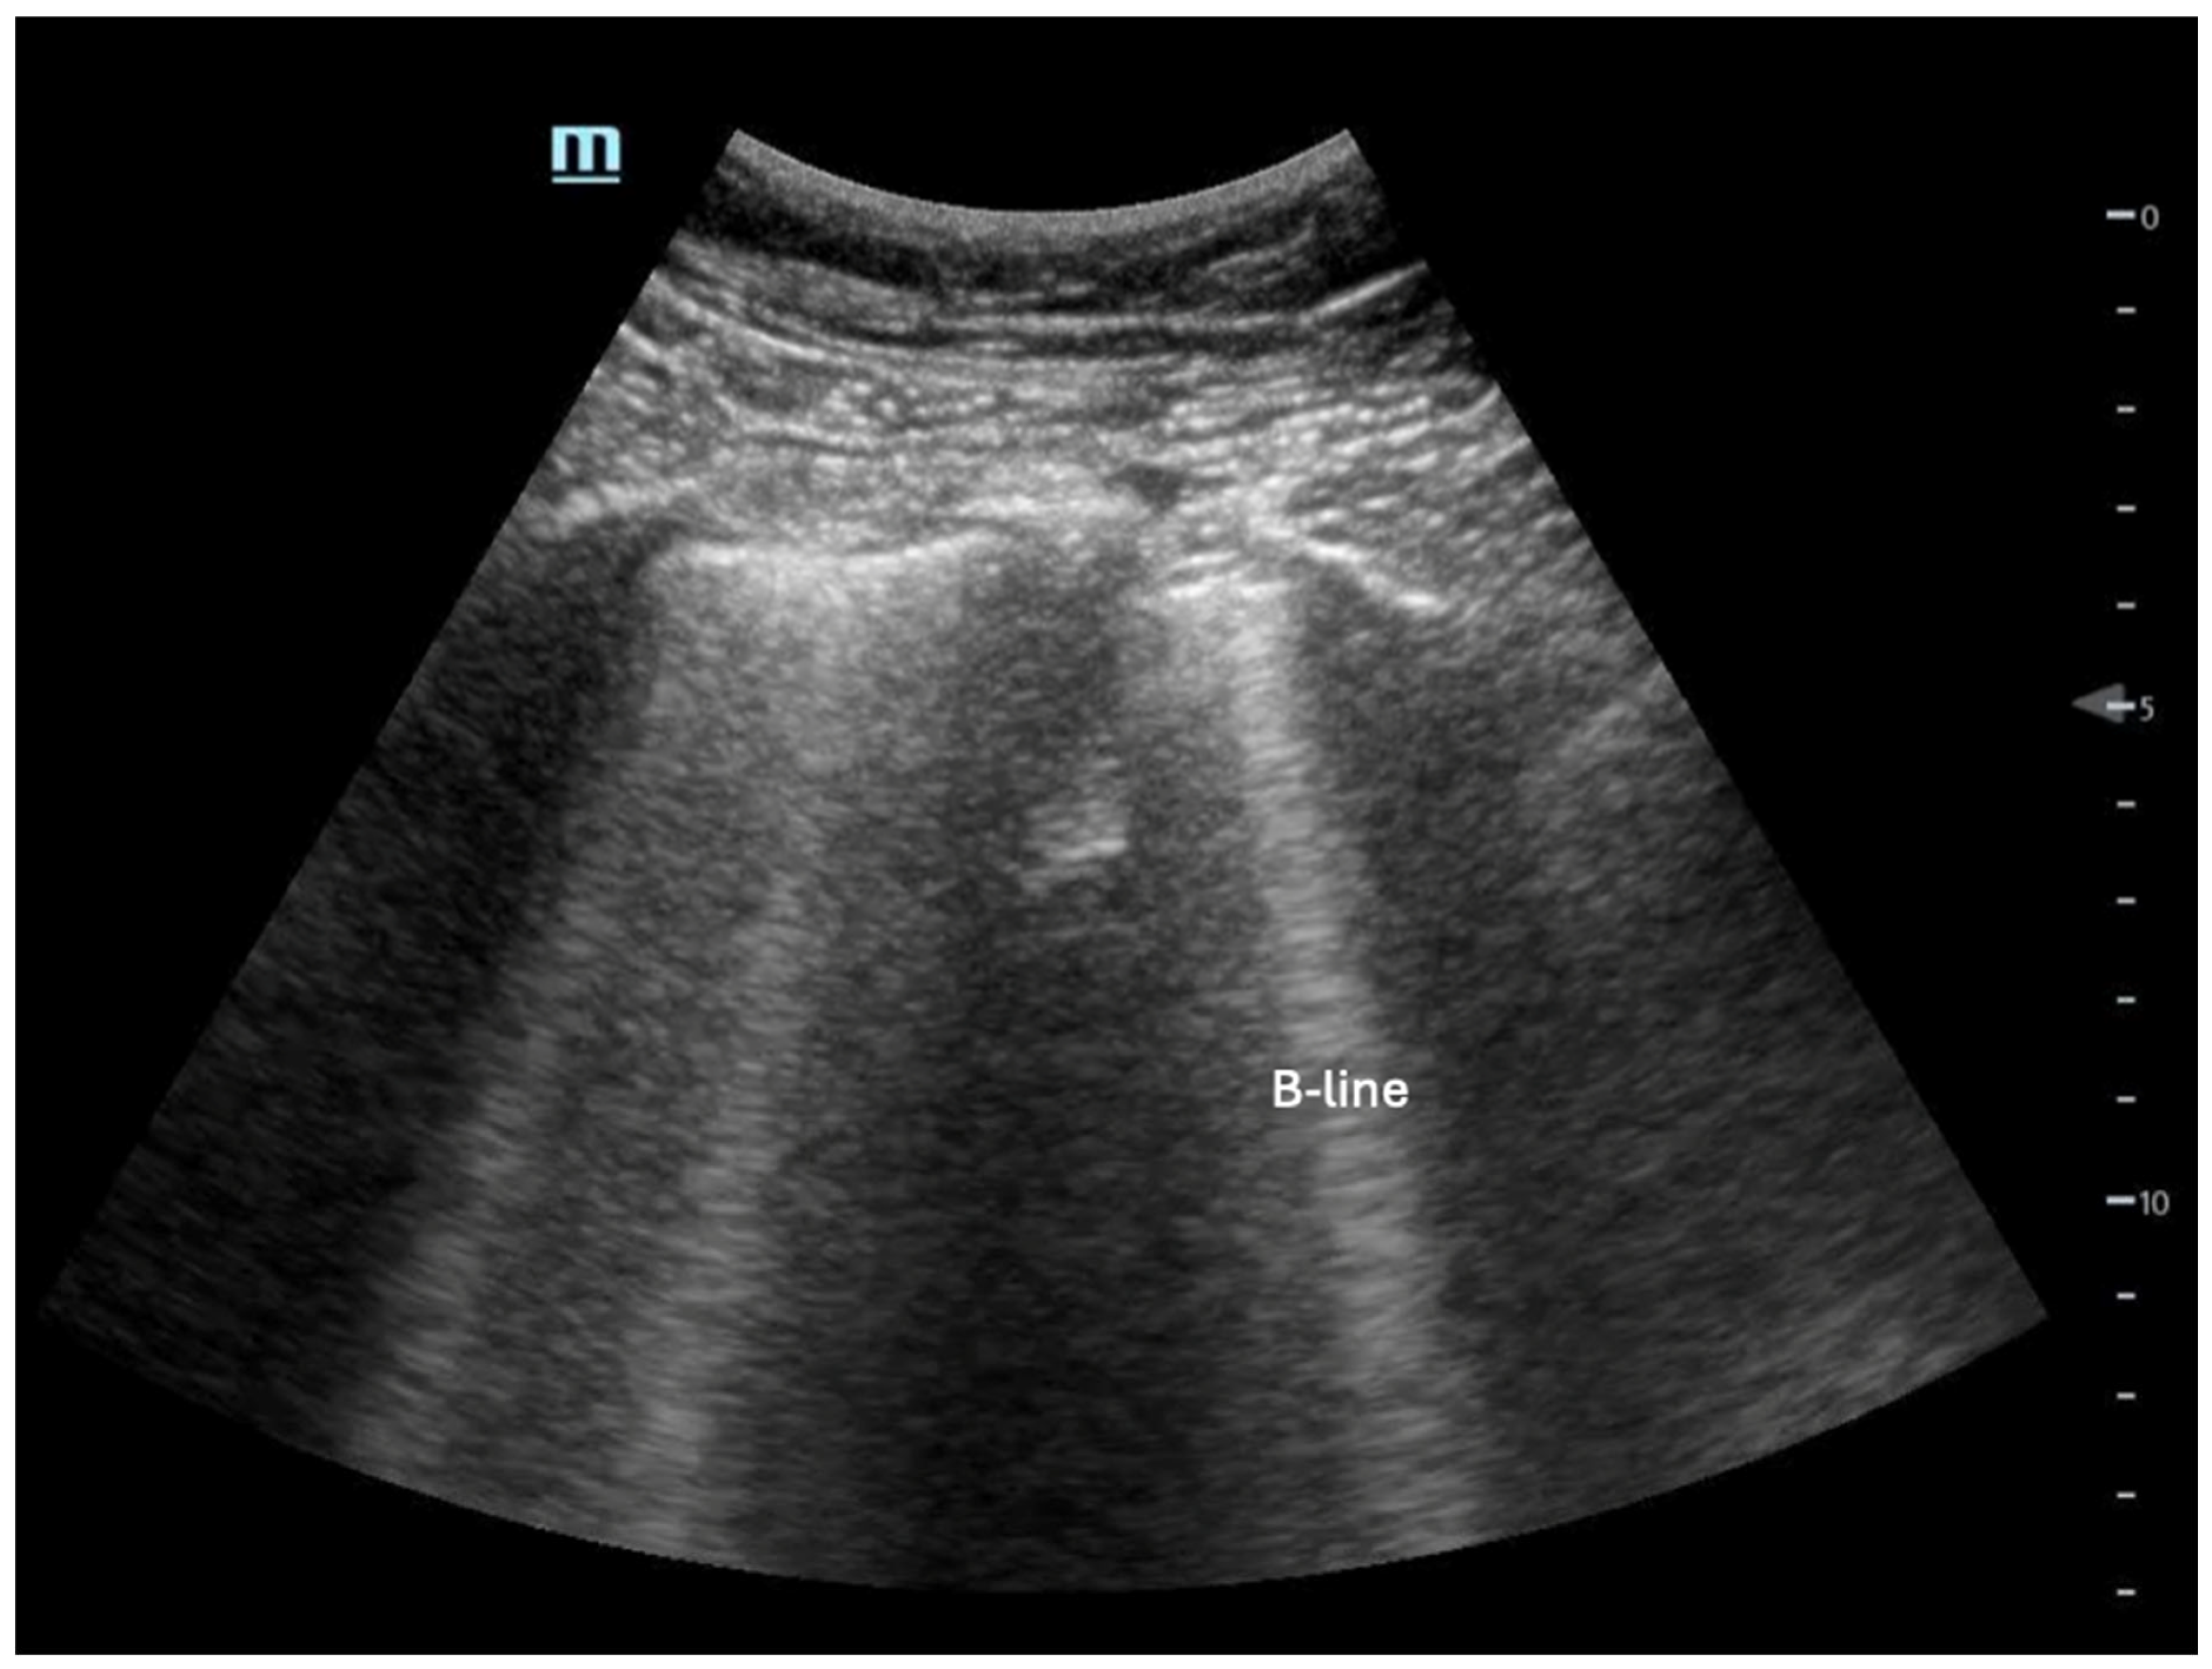

Extravascular lung water: This is indicative of LV congestion, which can be detected with high sensitivity by identifying B-lines on lung ultrasound [53] (Figure 10). The presence of three or more B-lines in an intercostal space across multiple lung fields suggests possible cardiogenic pulmonary edema, though alternative causes, such as acute respiratory distress syndrome (ARDS) or interstitial lung disease, should also be considered. Pathologic B-lines are vertical, hyperechoic artifacts extending from the pleural line to the deep lung parenchyma, disrupting normal A-lines. Distinguishing true B-lines from comet-tail artifacts is essential, as comet-tails also originate from the pleural line but do not extend as deeply. Additionally, isolated B-lines (1–2 per lung field) may be a normal finding and should not be overinterpreted. A systematic lung ultrasound assessment, combined with clinical correlation, is crucial for differentiating cardiogenic from non-cardiogenic pulmonary edema.

Figure 10.

Example of B-lines, which are discrete vertical hyperechoic artifacts that originate at the pleural line and extend to the bottom of the screen.